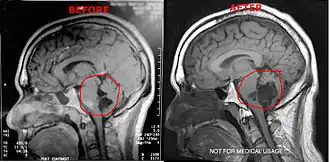

Magnetic resonance imaging (MRI) and computed tomography (CT) brain scans can be used to identify these tumors.

Treatment to remove these tumors always involve radical surgery. The reported recurrence rate for a subtotal removal is 30% after a mean interval period of 8.1 years.[4] Surgery is the primary treatment for removal of the brain tumor. Use of an endoscope may assist on obtaining a more complete surgical removal from hidden recesses.[5]

It has been seen that a few patients have tumors that grow unusually fast, especially after surgery. After surgery it is highly suggested the patients get quarterly MRI's to monitor their tumors or as per neurosurgeons/neurologists order. If monitoring the tumor, it is suggested to use the same facility for each scan. Using different facilities can result in minor variations in the scan which can result in false measurements of the brain tumor.